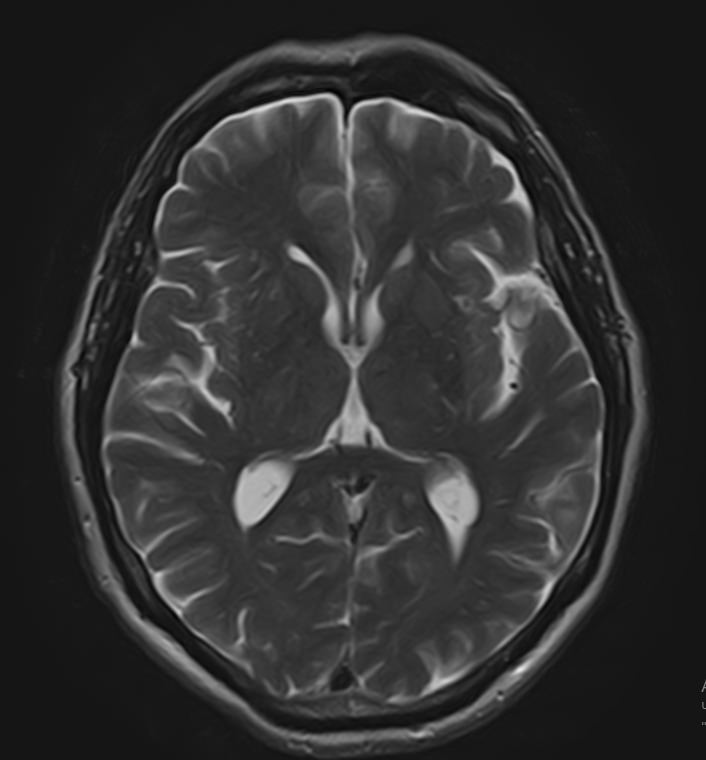

Для диагностики поражения черепно-мозговых нервов, а также оценки состояния окружающих их тканей и визуализации сосудистой сети головного мозга в клинике «Доступная медицина» проводится комплексное обследование МРТ головного мозга + Мр-ангиография головного мозга + МР-венография головного мозга + черепно-мозговые нервы. Данное обследование включает в себя несколько протоколов: стандартный – для оценки состояния всех структур головного мозга и дополнительные – для изучения очагов поражения черепных нервов и визуализации всей сосудистой системы головного мозга.

Исследования выполняются на современном высокопольном томографе экспертного класса TOSHIBA VANTAGE TITAN 1,5 Тесла, который использует разные режимы сканирования с толщиной среза от 1мм в различных плоскостях с последующей цифровой обработкой полученных данных для создания трехмерных изображений. МР-ангиография отображает состояние артериальной системы кровоснабжения головного мозга. МР-венография головного мозга позволяет детально изучить особенности венозного русла головного мозга.

Компьютерная программа обрабатывает данные, полученные при сканировании, и формирует объемные изображения как самого мозга, так и сосудистой системы в отдельности без прилегающих тканей. Методики применяются одновременно и взаимодополняют друг друга.

• злокачественные и доброкачественные новообразования, которые могут быть либо первичной опухолью черепно-мозгового нерва, либо произрастать из окружающих тканей головного мозга и сдавливать волокна близлежащего нерва;

• демиелинизирующие заболевания (при которых повреждается миелиновая оболочка нейронов), например, рассеянный склероз;

• воспалительные и инфекционные процессы (невриты, поражения некоторых черепных нервов на фоне воспаления среднего уха, энцефалиты, менингиты);

• повреждения нервов на фоне черепно-мозговых травм (разрывы нервов, кровоизлияние, сдавление гематомой);

• поражения черепных нервов на фоне ишемического или геморрагического инсульта;

• патология нервов на фоне сосудистых проблем (вазоневральный конфликт — сдавление нерва близлежащим сосудом, также на фоне патологической извитости, аневризмы, сосудистой мальформации).